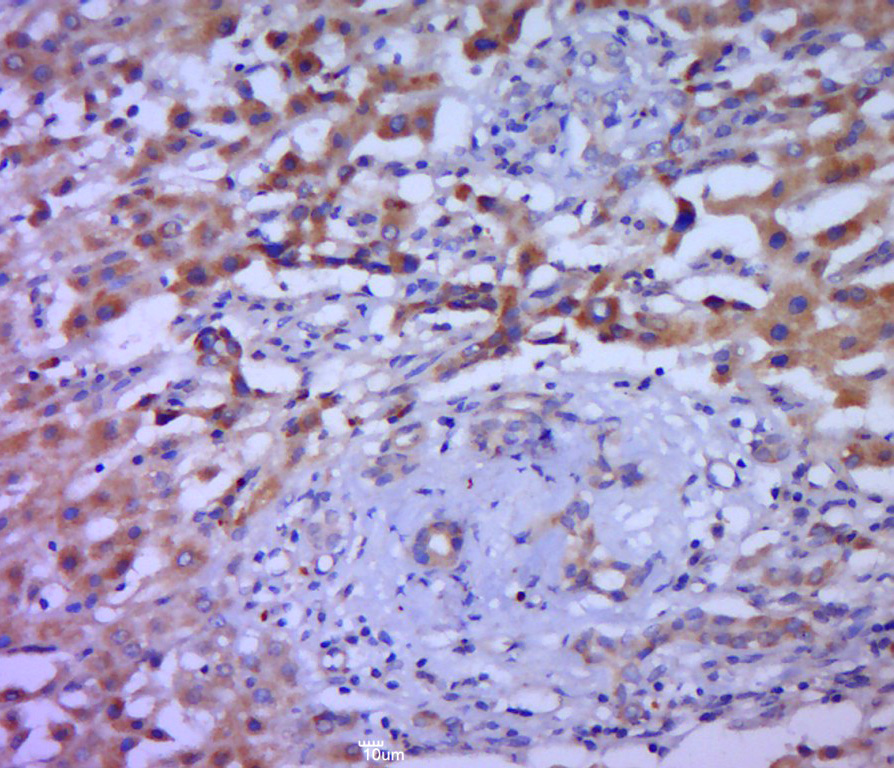

Paraformaldehyde-fixed, paraffin embedded (human liver carcinoma); Antigen retrieval by boiling in sodium citrate buffer (pH6.0) for 15min; Block endogenous peroxidase by 3% hydrogen peroxide for 20 minutes; Blocking buffer (normal goat serum) at 37°C for 30min; Antibody incubation with (IL-1 Alpha) Polyclonal Antibody, Unconjugated (bs-4946R) at 1:400 overnight at 4°C, followed by a conjugated secondary (sp-0023) for 20 minutes and DAB staining.

Paraformaldehyde-fixed, paraffin embedded (human colon carcinoma); Antigen retrieval by boiling in sodium citrate buffer (pH6.0) for 15min; Block endogenous peroxidase by 3% hydrogen peroxide for 20 minutes; Blocking buffer (normal goat serum) at 37°C for 30min; Antibody incubation with (IL1A) Polyclonal Antibody, Unconjugated (bs-4946R) at 1:400 overnight at 4°C, followed by a conjugated secondary (sp-0023) for 20 minutes and DAB staining.